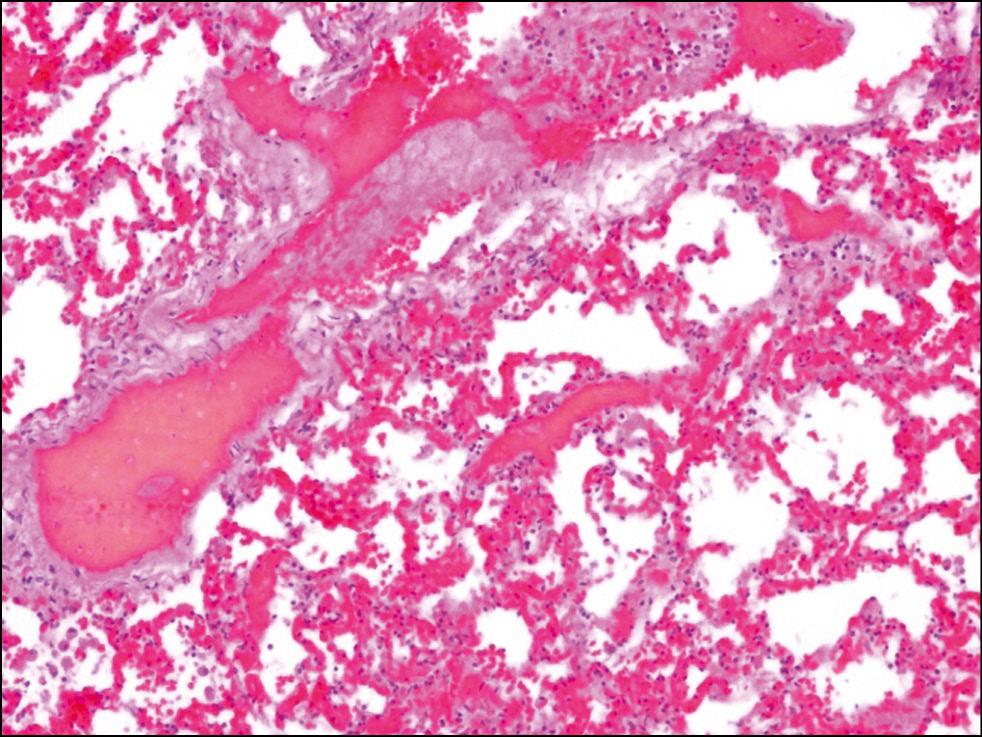

Гистологическое исследование. При гистологическом исследовании во всех органах отмечалось резкое полнокровие не только в крупных сосудах, но также в артериолах и венулах с развитием агрегации (сладжа) эритроцитов, явлениями внутрисосудистого гемолиза и формированием гомогенных жёлто-бурых масс, повторявших, как слепки, очертания сосудов (рис. 1).

Рис. 1. Резкое полнокровие сосудистого русла с развитием сладжа и потерей очертания эритроцитов, формированием гомогенных жёлто-бурых масс (внутрисосудистый гемолиз). Окраска гематоксилином и эозином, ×100. / Fig. 1. Massive plethora of blood vessels with the development of sludge and loss of outline of red blood cells with the formation of homogeneous yellow-brown masses (intravascular hemolysis). Hematoxylin-eosin, ×100.